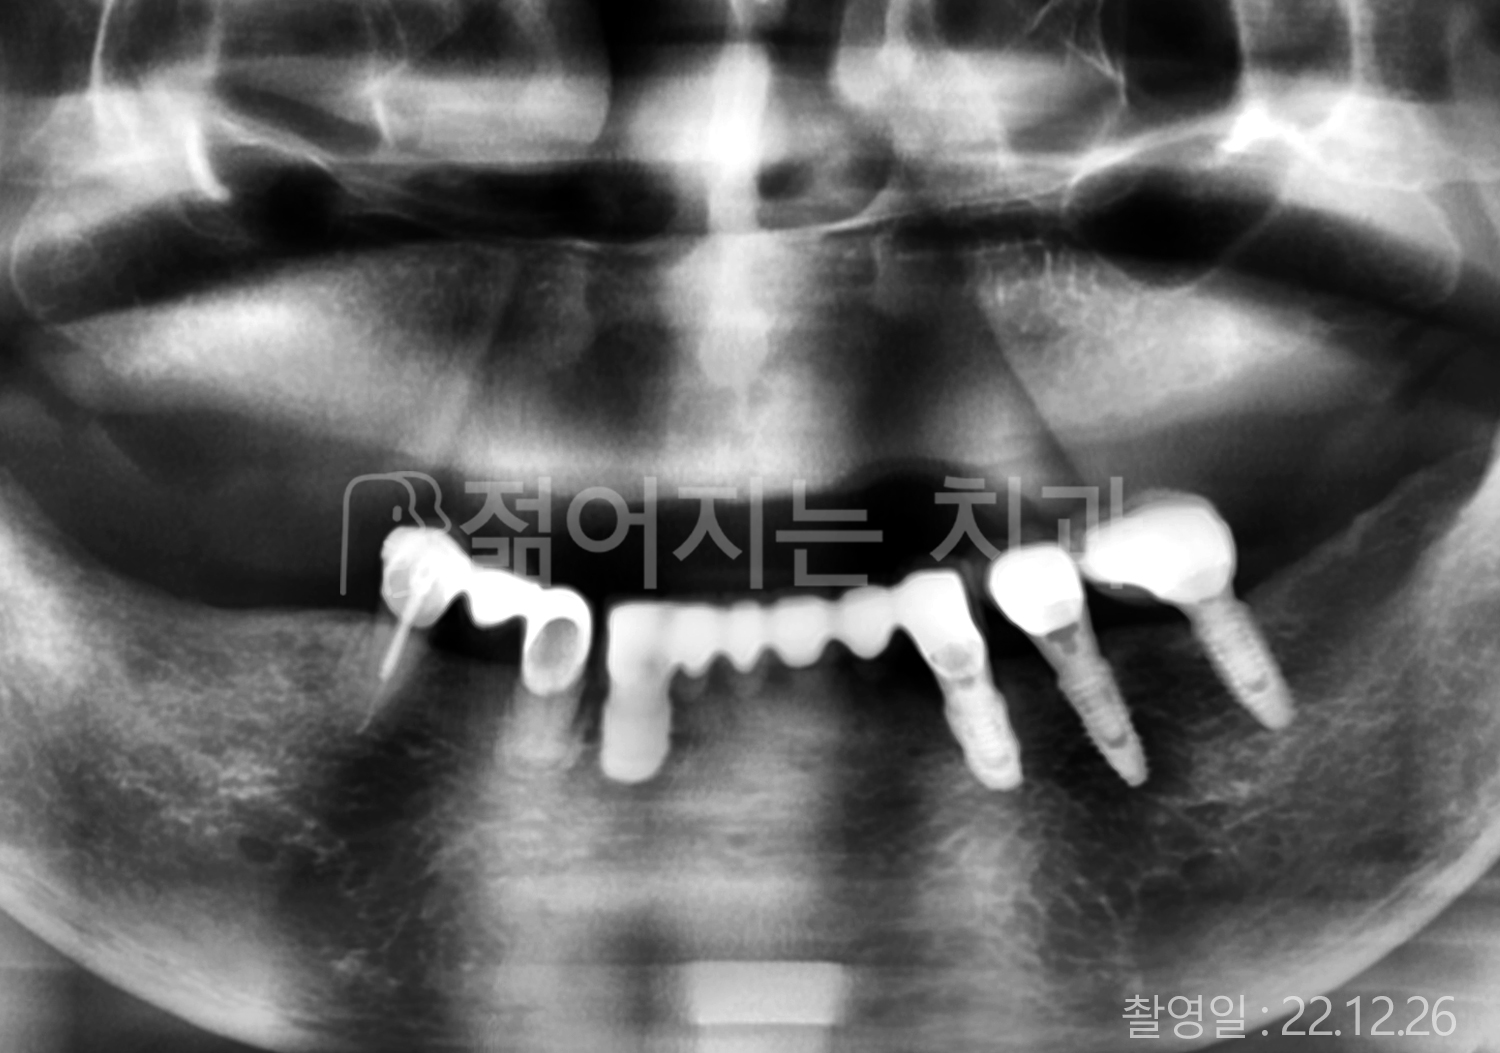

• 60대 고혈압, 고지혈증 전체치아 10개 이상 임플란트

• 70대 전체치아 10개 이상 임플란트

• 60대 전체치아 10개 이상 임플란트

• 50대 전체치아 10개 이상 임플란트

• 50대 고혈압, 고지혈증 전체치아 10개 이상 임플란트

• 60대 고혈압, 당뇨, 고지혈증 전체치아 10개 이상 임플란트

• 80대 고혈압, 당뇨, 골다공증 전체치아 10개 이상 임플란트

• 60대 고혈압 전체치아 10개 이상 임플란트

• 60대 고지혈증 전체치아 10개 이상 임플란트

• 60대 당뇨 전체치아 10개 이상 임플란트